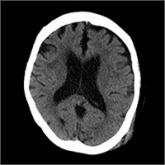

ArticleConfusion recurs 2 weeks after fallAuthor:Andrew Muck, MDPublish date: October 2, 2017Initial head and neck CT scans following a syncopal episode were unrevealing. Two weeks later, a follow-up scan painted a different picture.Read More